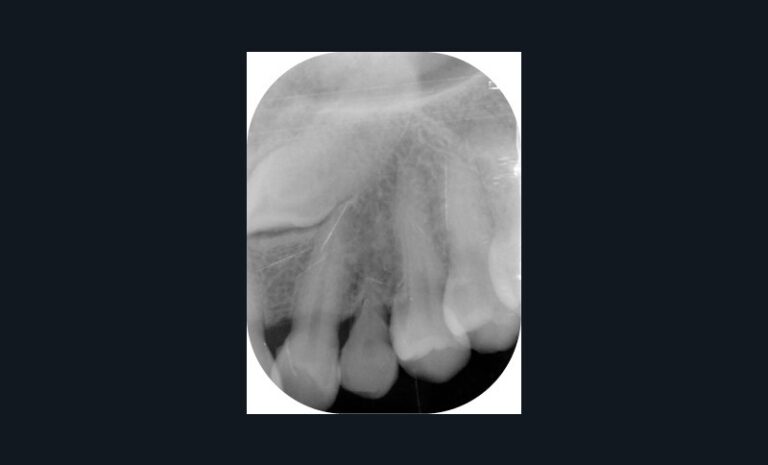

Dans l’exemple (fig. 1 et 2), la patiente présente une classe 1 molaire et classe 2 canine bilatérale sur un schéma normodivergent de classe 2 squelettique associé à une biproversion incisive et la canine 23 incluse.

Avec les aligneurs que je programme, la première phase de traitement consiste en un stripping de 0,5 mm de mésial molaire à distal canine afin de permettre une distalisation des prémolaires et canines pour obtenir un gain possible de 1,5 mm en mésial des canines avant l’étape d’alignement incisif.